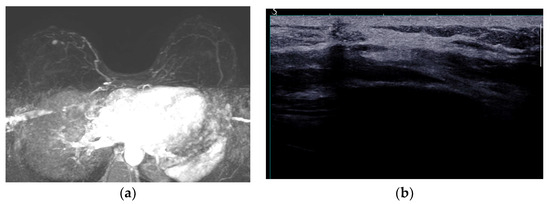

5.2.6. Breast Implant Associated Atypical Large Cell Lymphoma (BIA-ALCL)

- Sharma, B.; Jurgensen-Rauch, A.; Pace, E.; Attygalle, A.D.; Sharma, R.; Bommier, C.; Wotherspoon, A.C.; Sharma, S.; Iyengar, S.; El-Sharkawi, D. Breast Implant-associated Anaplastic Large Cell Lymphoma: Review and Multiparametric Imaging Paradigms. Radiographics 2020, 40, 609–628. [Google Scholar] [CrossRef] [PubMed]

- Adrada, B.E.; Miranda, R.N.; Rauch, G.M.; Arribas, E.; Kanagal-Shamanna, R.; Clemens, M.W.; Fanale, M.; Haideri, N.; Mustafa, E.; Larrinaga, J.; et al. Breast implant-associated anaplastic large cell lymphoma: Sensitivity, specificity, and findings of imaging studies in 44 patients. Breast Cancer Res. Treat. 2014, 147, 1–14. [Google Scholar] [CrossRef] [PubMed]

- Rotili, A.; Ferrari, F.; Nicosia, L.; Pesapane, F.; Tabanelli, V.; Fiori, S.; Vanazzi, A.; Meneghetti, L.; Abbate, F.; Latronico, A.; et al. MRI features of breast implant-associated anaplastic large cell lymphoma. Br. J. Radiol. 2021, 94, 20210093. [Google Scholar] [CrossRef]